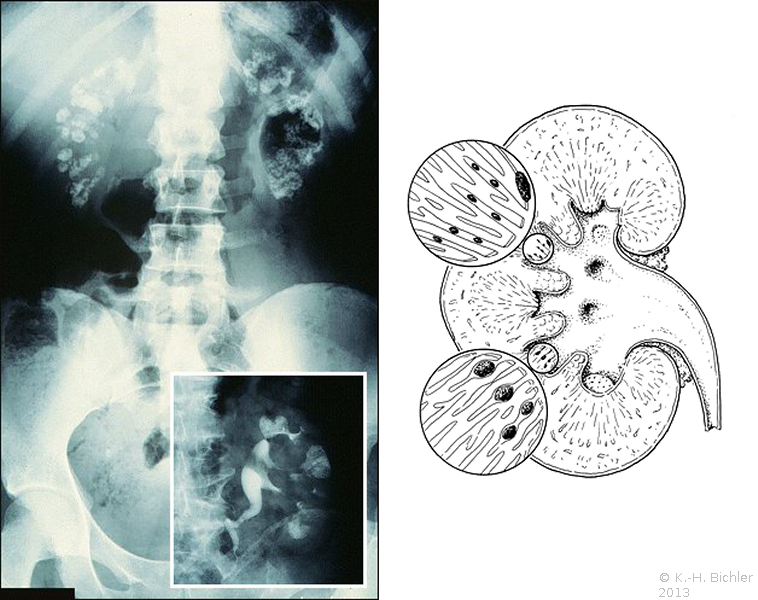

Die Markschwammniere ist eine kongenitale Erkrankung mit autosomal rezessivem Erbgang. Eine Verwandtschaft mit der polyzystischen Nierendegeneration wird angenommen. Pathogenetisch ist eine zystische Degeneration der distalen Sammelrohre zu vermuten. Die Markschwammniere kann sämtliche Kelche beider Nieren aber auch nur einer Niere oder auch nur die Sammelrohre eines Kelches betreffen. Die Markschwammnieren neigen zur Harnsteinbildung. Die Ursachen dafür sind Defekte im distalen Nierentubulus und zwar in ca. 40% in Form einer renalen tubulären Azidose.

Die renale tubuläre Azidose (RTA) unterhält durch das alkalische Urin-pH und die Hypozitraturie eine rezidivierende Harnsteinbildung

(s. Azidifierungsstörungen). Bei der Harnsteinanalyse werden überwiegend Struvit, Karbonatapatit und Kalziumoxalat gefunden

Das Schema zeigt die zystisch erweiterten Sammelrohre mit multiplen Steinbildungen (Abbildung 1).